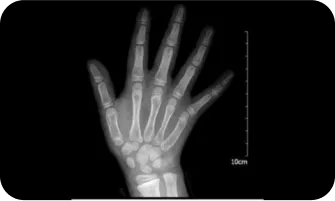

02

엑스레이 검사를 이용한

여아의 골연령검사

300점

400점

8.5세

500점

10세

600점

11세

700점

12세

800점

13 ~ 14세

900점

14 ~ 15세

1000점

15세 ~